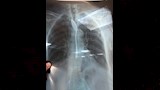

وباشر الفريق الطبي الفحص السريع وإجراء الأشعة اللازمة، ثم نجح في استخراج المعلقة باستخدام منظار طبي دون مضاعفات، وسط متابعة دقيقة للحالة حتى تحسنت وسمح لها بالخروج في اليوم نفسه، بعد أن رافقها سبعة من أفراد أسرتها.